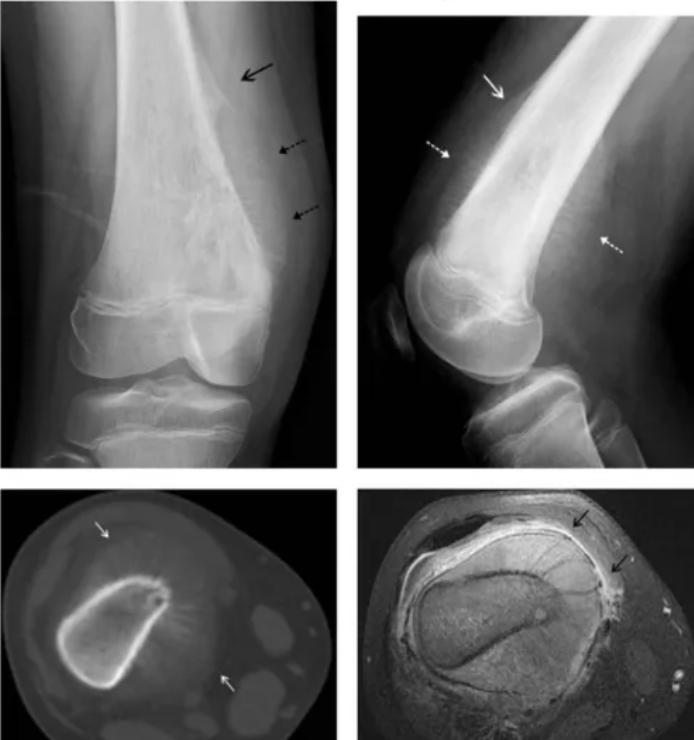

骨肉瘤是一種起源于間葉組織的惡性腫瘤,以能產(chǎn)生骨樣組織的惡性梭形基質(zhì)細(xì)胞為特征,又稱成骨肉瘤,是青少年最常見(jiàn)的原發(fā)惡性骨腫瘤,好發(fā)于四肢長(zhǎng)骨干骺端,其中一半以上的病例發(fā)生于膝關(guān)節(jié)周圍。它的出現(xiàn),就像一顆隱藏在身體里的定時(shí)炸彈,隨時(shí)可能給孩子的健康帶來(lái)嚴(yán)重威脅。

骨肉瘤的典型癥狀是疼痛和局部腫塊。早期疼痛多為持續(xù)性隱痛、鈍痛,很快就會(huì)發(fā)展為持續(xù)性劇痛,夜間疼痛更加明顯,且休息后難以緩解。隨著病情進(jìn)展,局部會(huì)出現(xiàn)腫塊,腫塊大小差別很大,表面皮膚溫度升高,淺靜脈充盈或怒張,部分患者還可能出現(xiàn)病理性骨折。此外,骨肉瘤還可能引發(fā)全身癥狀,如發(fā)熱、消瘦、貧血等。

檢查結(jié)果:生長(zhǎng)痛各項(xiàng)檢查通常無(wú)異常;骨肉瘤通過(guò)影像學(xué)檢查(如X線、CT、MRI等)可發(fā)現(xiàn)骨質(zhì)破壞、瘤骨形成等異常表現(xiàn)。